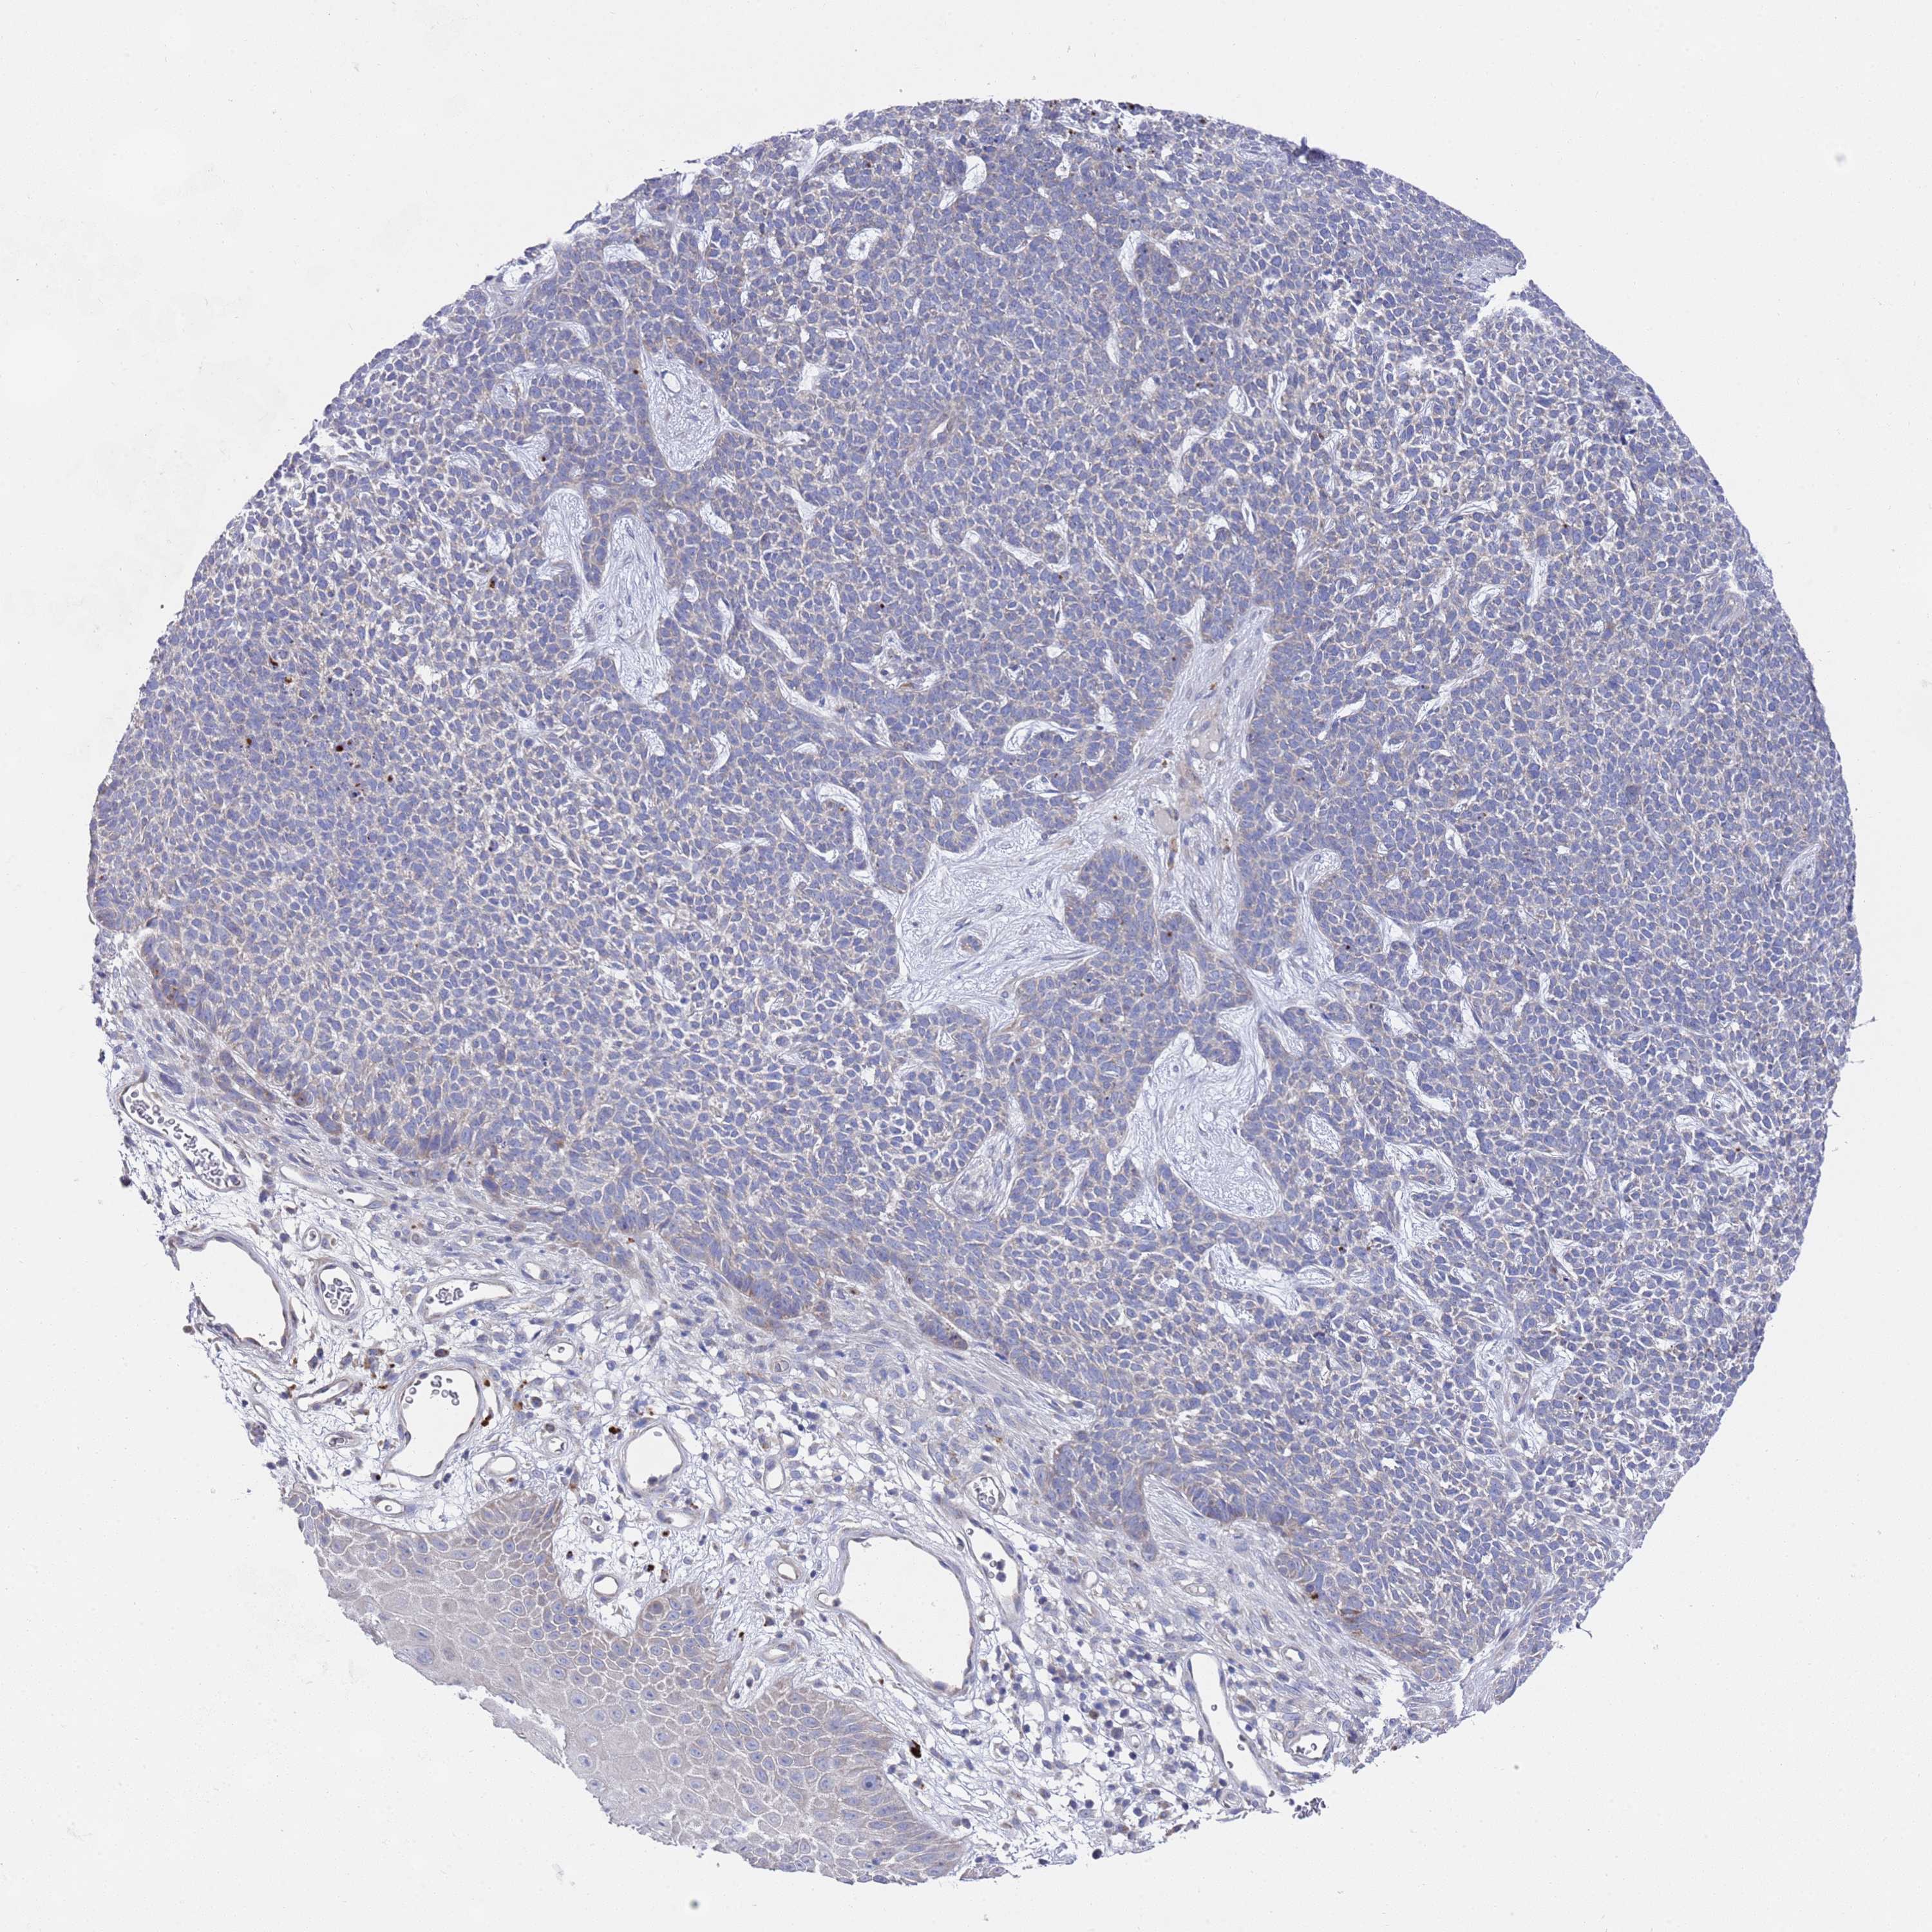

SKIN CANCER - Protein expressioni

A mouse-over function shows sample information and annotation data. Click on an image to view it in a full screen mode. Samples can be filtered based on level of antibody staining by selecting one or several of the following categories: high, medium, low and not detected. The assay and annotation is described here.

Each image is clickable and will lead to virtual microscopy that enables deeper exploration of all samples and also displays staining intensity scores, fraction scores and subcellular localization as well as patient and tissue information for each sample.

Antibody HPA021453

Squamous cell carcinoma, NOS